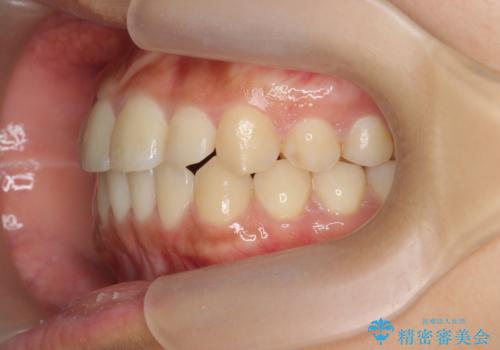

前歯のねじれ、すれ違いを改善 部分ワイヤー+マウスピース矯正

- 上下前歯のすれ違い、ねじれのある歯並びの矯正治療を求めて来院されました。

上顎前歯のみの部分ワイヤー治療を約6ヶ月行い、ねじれの問題を解決したのち、マウスピース矯正で細かな歯列を整えていきます。

前歯のすれ違いが改善することで噛みやすくなった。と矯正治療の結果に満足いただくことができました。